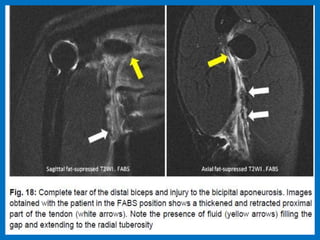

Short head (white arrow). Note the presence of fluid signal filling the tendinous gaps.

Findings are far more conspicuous in the FABS position.

Biceps tendon tear.

Complete tear of distal biceps tendon.

Short head (whitearrow). Note the presence of fluid signal filling the tendinous gaps. Findings are far more conspicuous in the FABS position.

Complete tear ofdistal biceps tendon.